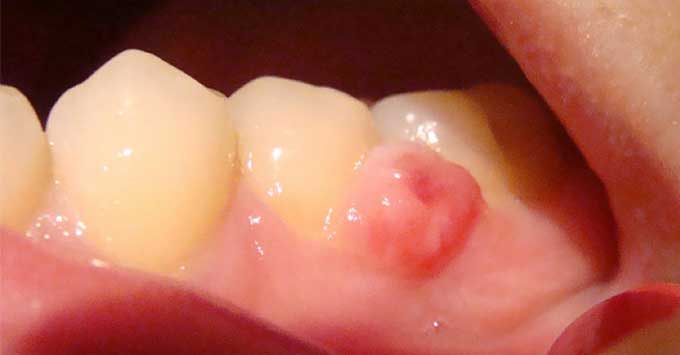

Ангиоматозный

Представляет собой скопление в фиброзной ткани тучных клеток и кровеносных воспаленных сосудов с очень тонкими стенками. Основная причина его появления – частое травмирование слизистой. Локализуется около зубной шейки и может образовываться на любой челюсти.

Имеет совершенно гладкую или немного бугристую поверхность, красный цвет, мягкую консистенцию, развивается быстро и вызывает сильную кровоточивость даже от незначительного его травмирования. После удаления присутствует большая вероятность его повторного образования.

Разрастание тканей чаще наблюдается у детей, подростков и женщин в период беременности.